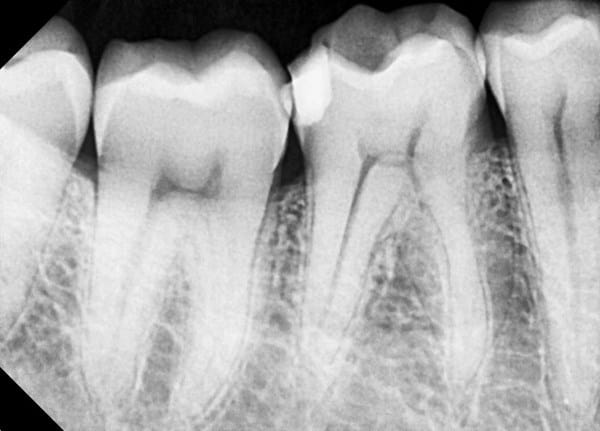

¿Necesitare empaste, endodoncia o algo diferente?

Decir que: no siento nada ni al frio ni al calor, ni al cepillarme los dientes, me duele solo al morder algo duro, como por ejemplo carne de ternera, aunque hoy me dio golpes en todas las muelas y me dolía en dos de ellas también

Llevo tres días con estas molestias, si no como nada, no siento nada y cuando como chicle, se me queda como pegado en una muela de abajo